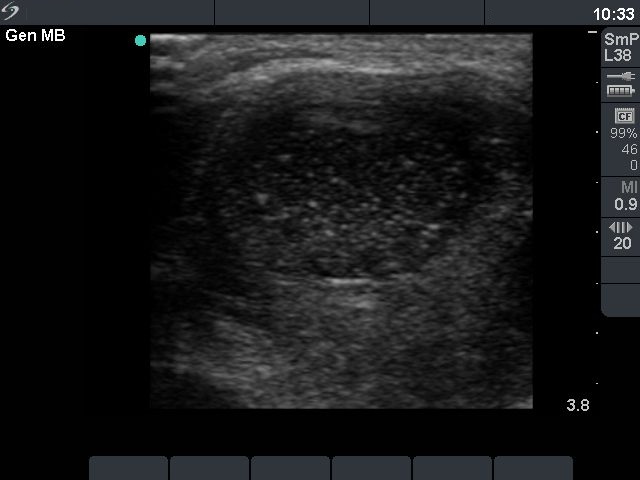

Three days after the fourth session (second row):

Clinical presentation: 3 days after the fourth session of the ethanol treatment: the cyst became more enlarged and painful. The body temperature rose to 38.2 C, the erythrocyte sedimentation rate was 50 mm/H.

Ultrasonography: the size of the nodule was 30x25x34 mm, and another hyperechogenic lesion was found dorsal to the treated lesion.